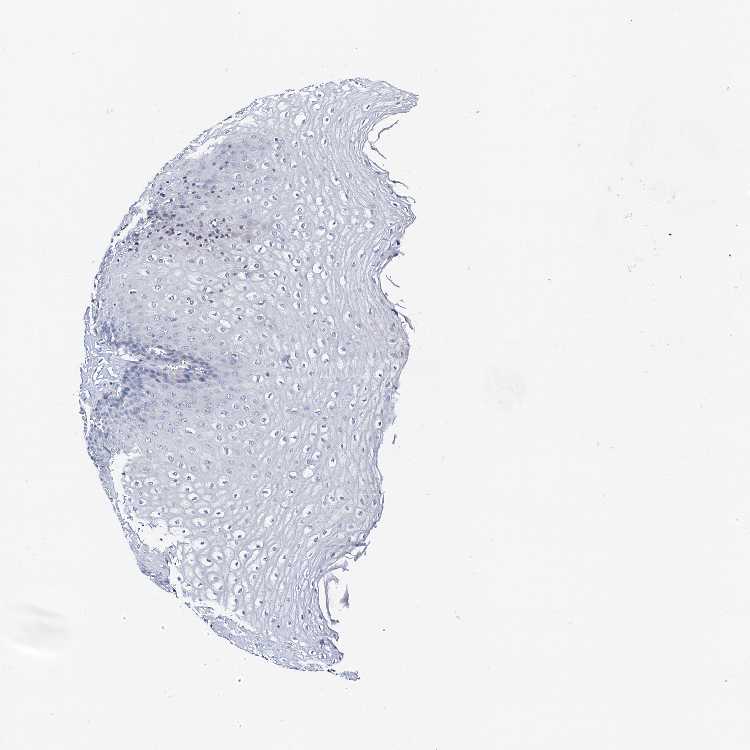

ESOPHAGUS - Antibody stainingi

Antibody staining in the annotated cell types in the current human tissue is reported as not detected, low, medium, or high, based on conventional immunohistochemistry profiling in selected tissues. This score is based on the combination of the staining intensity and fraction of stained cells.

Each image is clickable and will lead to virtual microscopy that enables deeper exploration of all samples and also displays staining intensity scores, fraction scores and subcellular localization as well as patient and tissue information for each sample.

Antibody HPA001333Antibody CAB034046

Squamous epithelial cells Not detectedNot detected